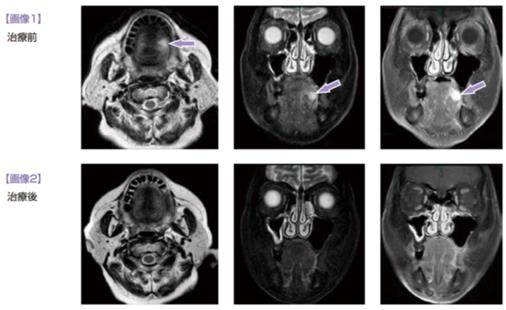

免疫細胞療法之舌癌

83歲女性,2011年2月因舌左側糜爛赴綜合醫院就診,診斷舌鱗癌cT2, cN0, cM0, cStⅡ。標準療法... -